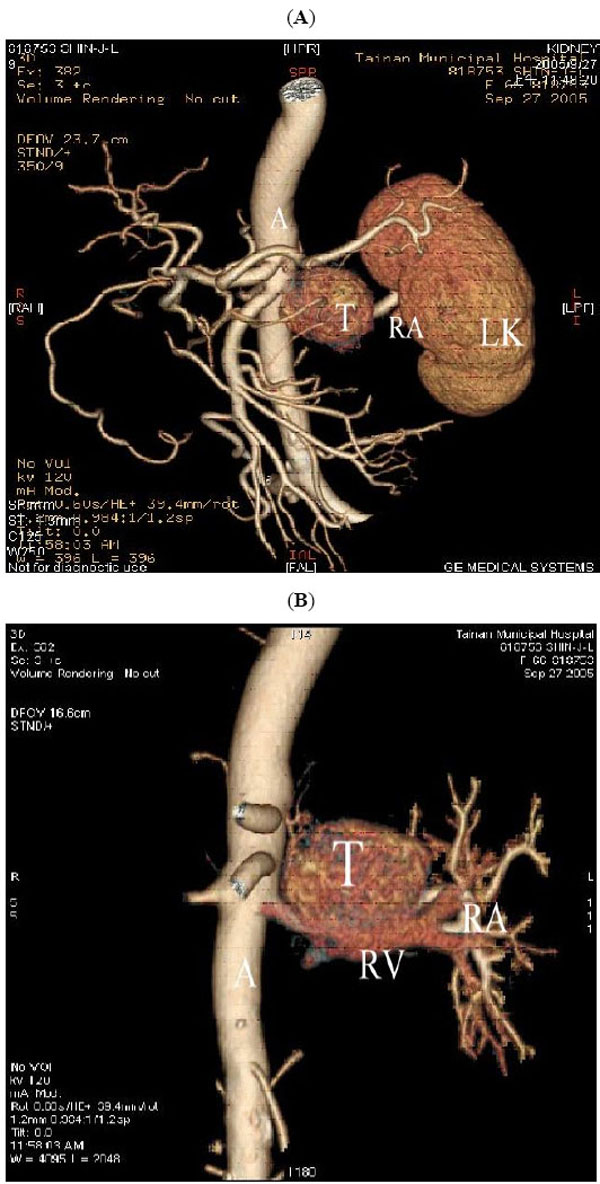

A 3.6x 3.7cm retroperitoneal mass was found incidentally by renal ultrasonography (Fig. 1). CT scan showed an enhanced tumor 4.5x3.5x4.0cm in size (Fig. 2). The tumor was located in the left suprarenal space indicating an adrenal tumor. 64-slice CT revealed that the tumor mass was just between the renal artery and the renal vein (Figs. 3A, 3B). Preoperative CT-guided biopsy revealed pheochromocytoma. Urine catecholamine was 3.44 mg/24 hr (normal 1.0-7.5mg/24hr) and plasma renin was 3.03mol/L (normal 0.5-5.7mol/L).

(A) and (B) 64-slice CT with 3D reconstruction, showing the tumor mass (T) seen between renal artery (RA) and renal vein (RV). (A represents aorta and LK represents left kidney).